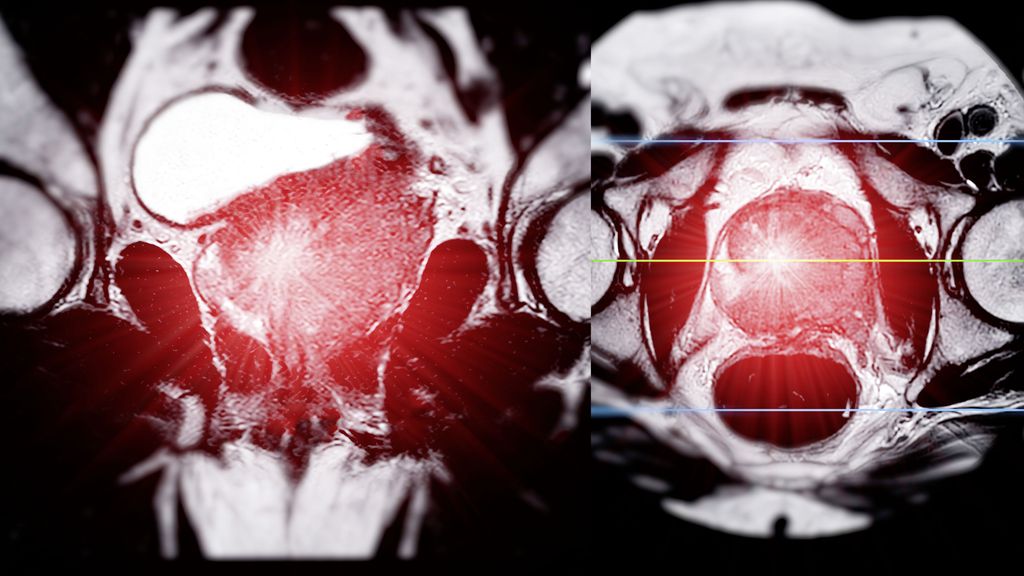

Le paysage thérapeutique des tumeurs urologiques est en constante évolution. Les progrès les plus marquants concernent les premières lignes de traitement. Voici un aperçu des études qui ...